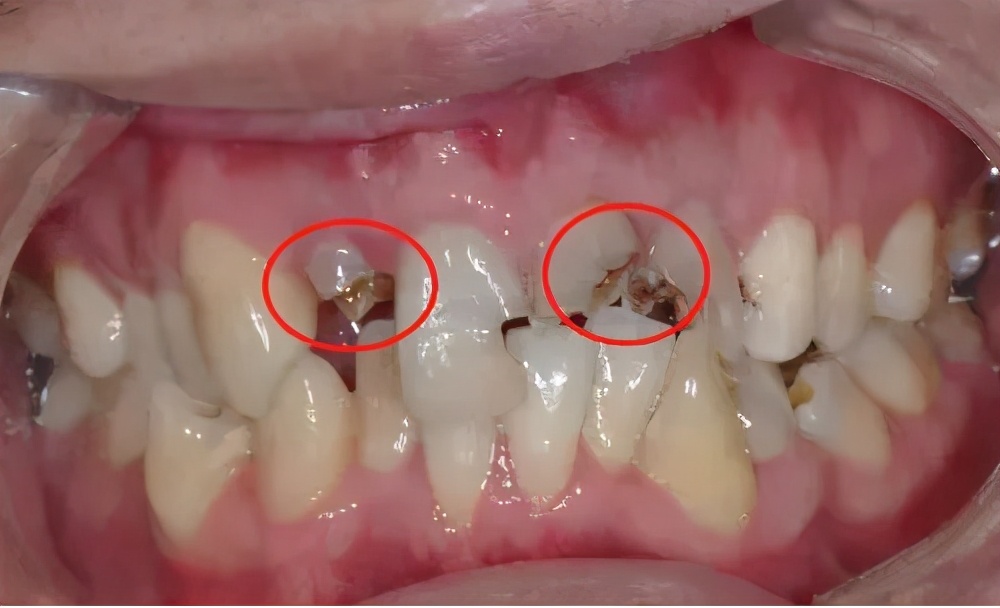

如果牙龈中的根足够长,通常可以进行核后冠。

由于只剩很少的牙齿组织,为了更好地固定牙齿,牙医会将牙桩插入根管中,在行业中我们称之为“牙桩”。

有些牙根短,如果单独修理,可能无法达到预期的效果。

这时,我们还可以将其与相邻的牙齿一起修复,以形成结合的牙冠,以增加牙齿的固位力和支撑力。

牙齿残根不疼就没事,别管它?!#雅悦齿科#

有些牙根太短,以至于即使使用后核冠也无法保存,因此医生会考虑使用覆盖义齿进行修复。